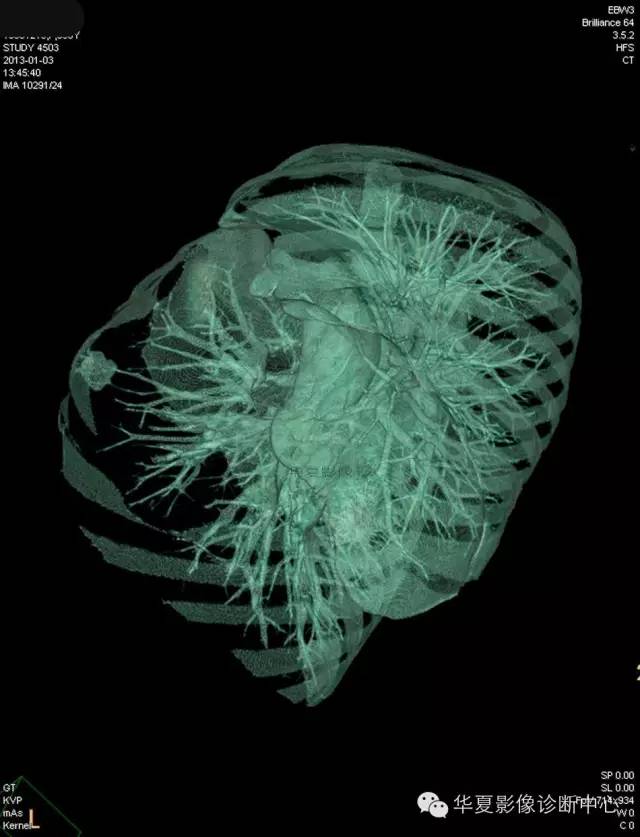

【病例学习】典型周围型肺癌CT病例一例

女,56岁,其父因肺癌去世,自觉胸部疼痛不适来诊要求拍胸片。

1.右肺上叶:肺组织1块,大小13×4×7cm。切面棕红色。2.右肺上叶肿物:灰白色组织一块,大小3×1×1.5cm。切面灰白色。3.右肺中叶结节:灰白色绿豆大组织1块。4.淋巴结:灰黑色绿豆大组织1块。

(右)肺中分化鳞状细胞癌。浸及胸膜。支气管残端切净。淋巴结未见癌转移(0/10)。